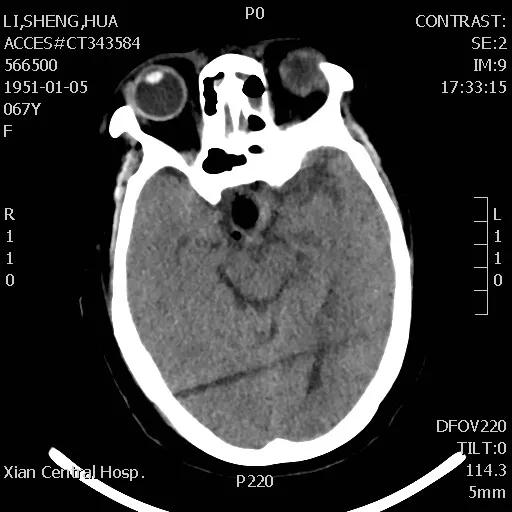

手术于次日下午进行,整个过程非常顺利,患者预后也非常理想,术后复查CT显示肿瘤切除干净,患者视力改善明显,经过一段时间的后续治疗,患者已痊愈出院。